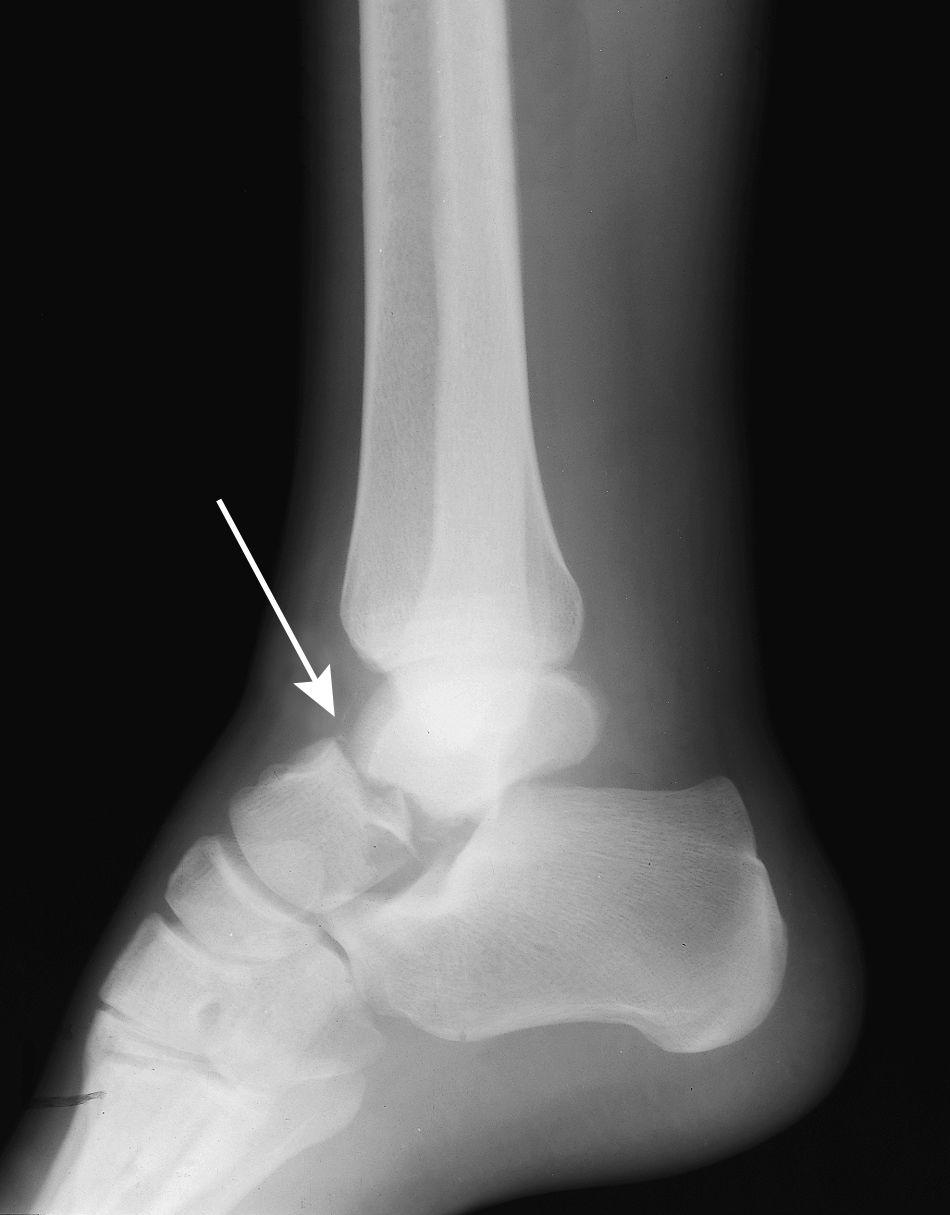

X-ray of a talus neck fracture.

An X-ray of a talus neck fracture.

Reproduced from Johnson TR, Steinbach LS (eds): Essentials of Musculoskeletal Imaging. Rosemont, IL American Academy of Orthopaedic Surgeons, 2004, p. 605.